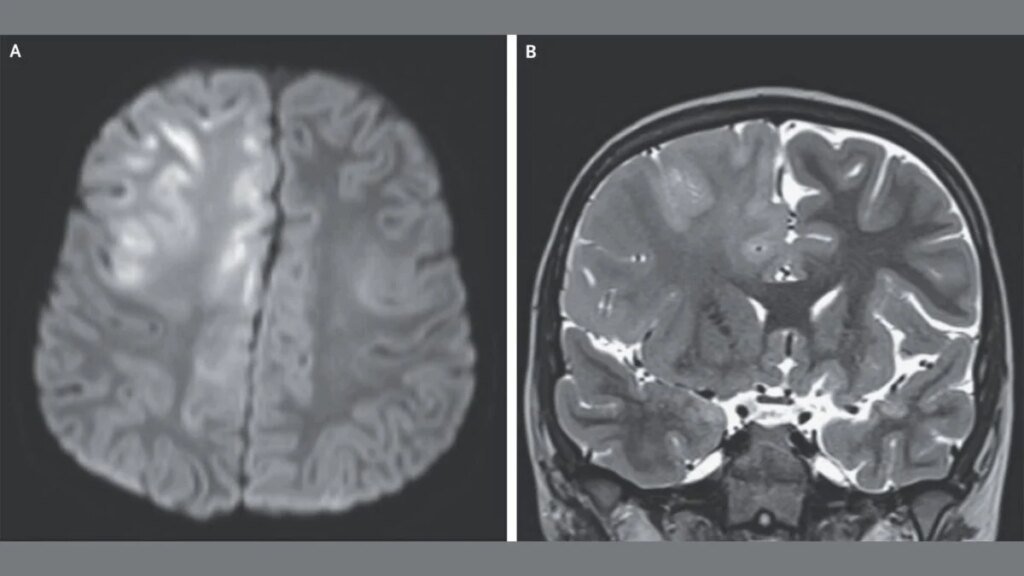

In this case, the 7-year-old boy visited the doctors three months into having seizures and cognitive decline. He was no longer able to speak, and an MRI scan (seen in the top image) revealed extensive damage to the brain. The boy had contracted measles at 7 months of age while living in Afghanistan, a country where the virus is endemic. Tests of his spinal fluid revealed high levels of antibodies to the measles virus. That, coupled with his infection history and EEG results, led doctors to diagnose him with SSPE.